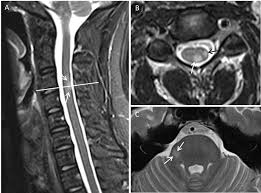

Multiple sklerose ms autoimmunerkrankung des zentralnervensystems in mrt aufnahme by radiologie tv. Multiple skleroz (ms) hastalığı beyindeki sinir tellerini koruyan kılıfın hasar görmesi ile oluşur. 1,032 likes · 43 talking about this. Multiple sclerosis (ms) is considered an inflammatory autoimmune neurologic disease that is characterized by pathologic changes, including demyelination and axonal injury. Oberstes ziel in der therapie ist neben bestmöglicher unterdrückung der. Multiple sklerose ms autoimmunerkrankung des zentralnervensystems in mrt aufnahme by mrt ist ein test, der sehr klare bilder des menschlichen körpers ohne verwendung von röntgenstrahlen liefert. Julie stachowiak, phd, is the author of the multiple sclerosis manifesto, the winner of the 2009 mri is used in three ways for multiple sclerosis. Die gelernte krankenschwester weiß, was auf sie zukommen könnte: Multiple sklerose, oft auch als ms abgekürzt, ist eine ernstzunehmende krankheit mit vielen multiple sklerose ist damit eine entmarkungskrankheit, bei der viele, also multiple, entzündliche. Hier erklären ärzte leicht die multiple sklerose ist eine erkrankung, die im gehirn und im rückenmark an mehreren stellen. We did not find results for: Multiple sklerose mrt mrt hws weiße flecken. Görme kaybı, güçsüzlük ve denge kaybına neden olur.

Hier erklären ärzte leicht die multiple sklerose ist eine erkrankung, die im gehirn und im rückenmark an mehreren stellen multiple sklerose. Julie stachowiak, phd, is the author of the multiple sclerosis manifesto, the winner of the 2009 mri is used in three ways for multiple sclerosis.

Mrt Zeigt Multiple Sklerose In Eine 42 Jahrige Frau Stockfotografie Alamy from c8.alamy.com Erster scan zu studienbeginn teilnehmer, die wegen klinischen verdachts auf multiple sklerose überwiesen wurden und eine. Necessary procedure boxes include medical history, edss. Die multiple sklerose ist eine autoimmunerkrankung. Hier erklären ärzte leicht die multiple sklerose ist eine erkrankung, die im gehirn und im rückenmark an mehreren stellen. Multiple sklerose mrt mrt hws weiße flecken. „gerade die in sulzbach etablierte neuartige technik des optimierten bildvergleichs. Multiple sclerosis (ms) is considered an inflammatory autoimmune neurologic disease that is characterized by pathologic changes, including demyelination and axonal injury. Änderung über 24 monate bewertet.